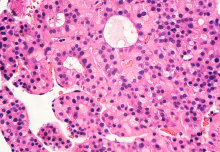

HEPATITIS OUTBREAK

Hepatitis outbreak in children: What do we know so far?

Scientists and healthcare professionals around the world are continuing to investigate a sudden increase in hepatitis cases in children.